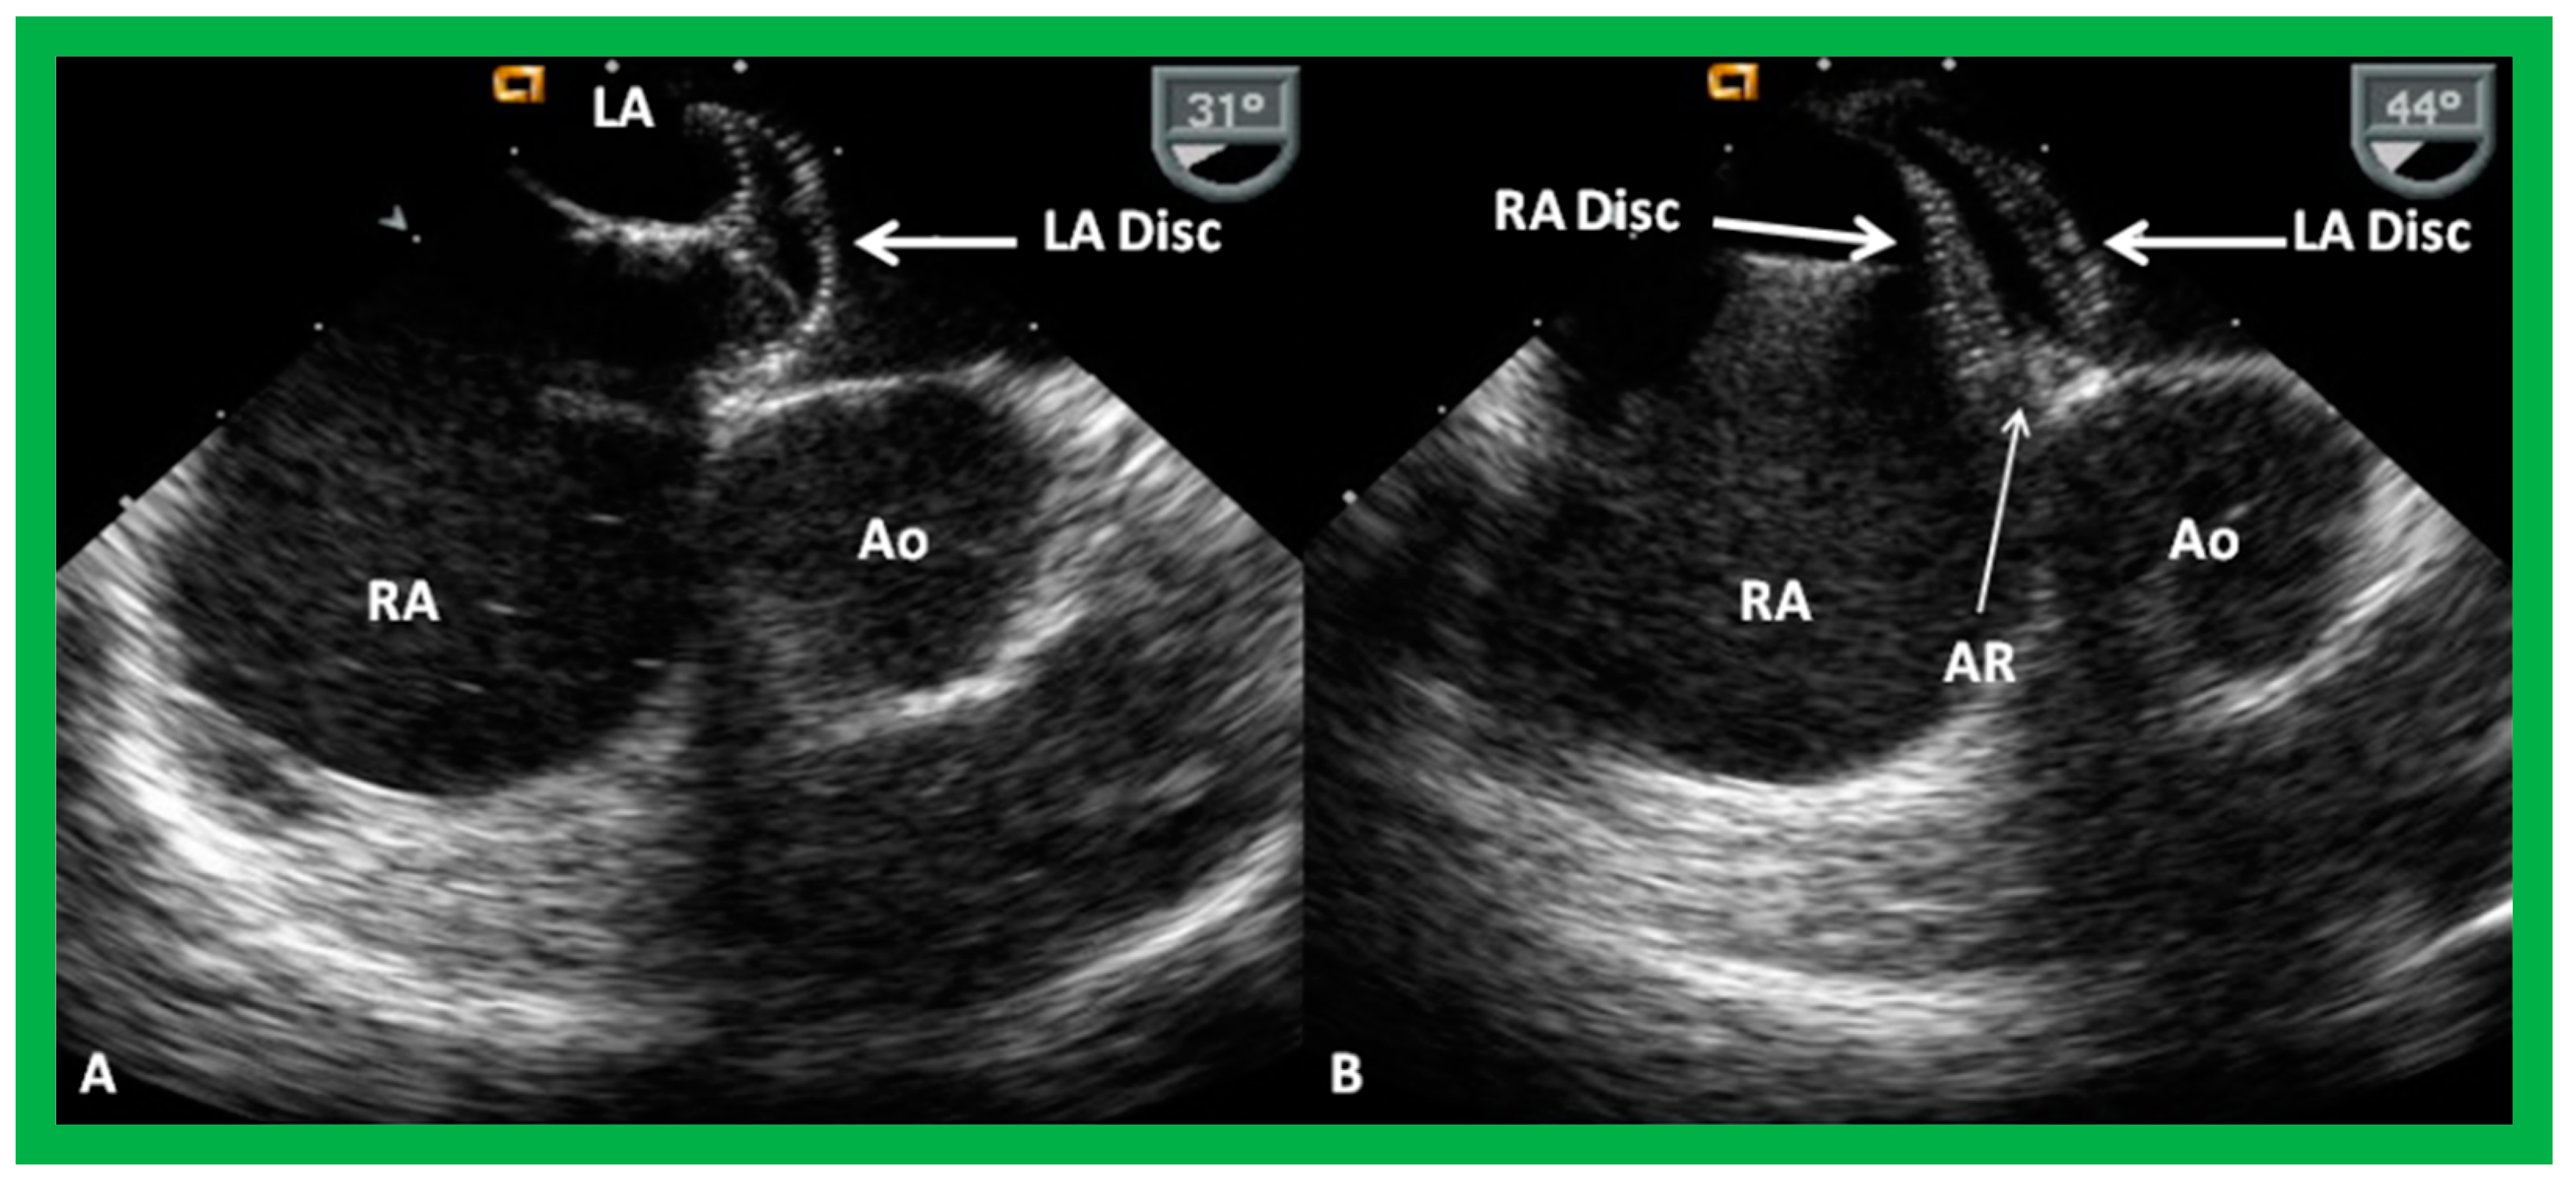

8.1. Amplatzer Septal Occluder

9.2. Device Position